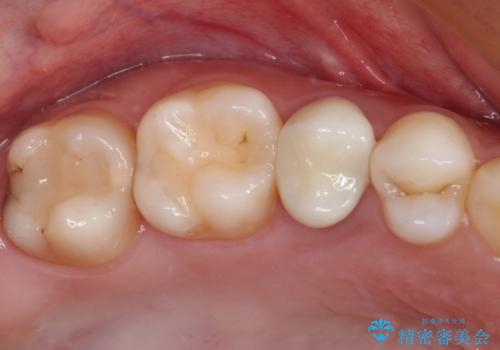

どちらの歯も痛みなどの症状はなく、治療後も異常所見なく経過をたどっています。

上顎大臼歯は向かい合った人から見えることはほとんどないため、切削量が少なく、適合の良いゴールドインレーが大変おすすめとなります。